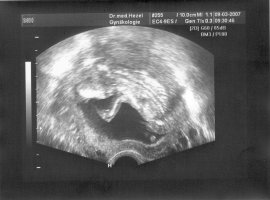

finde es ganz toll das sich immer mehr zusammen finden,heiße alle ganz herzlich willkommen,war gestern bei meiner FÄ,habe super tolle Fotos mitbekommen,habe die zwei schönsten raus gesucht,besondere obacht,auf das zweite,schaut manl genau zwischen die Beine,meine FÄ meinte das es sehr selten wäre es so früh zu sehen aber so eindeutig hätte sie es schon lange nicht mehr gesehen,sie sagte auch sofort das es zu 90 % ein kleiner MAX wird.Schaut selbst

.LG Sabrina

• Max die Erste.jpg

Max die Erste.jpg

36,9 KB · Aufrufe: 1.118

Laut Messungen ist der kleine schon ein ganz guter Brummer,5,8cm groß und 58 g schwer.

Und wie schon geschrieben ist es nicht üblich es so früh zu sehen aber es war einfach mehr wie eindeutig,man sah den hoden und den penis ja auch in anderfen einstellungen.

Ich würde es niemals bis zur geburt abwarten können,irgendwie ist das Baby nun kein einfaches Baby mehr sondern,unser Max.

LG Sabrina